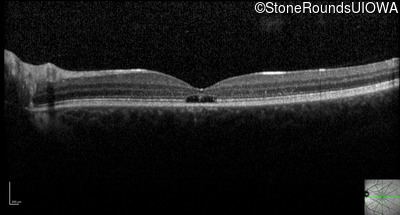

Optical Coherence Tomography - Right - 20/50 -2

Exemplar / OCT Stack

Optical Coherence Tomography - Left - 20/50 -1